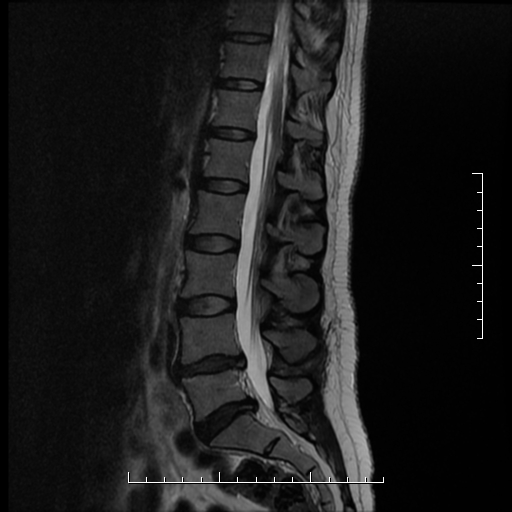

High-Resolution MRI

We deliver detailed, high-resolution MRI scans that support reliable and precise diagnostic results.